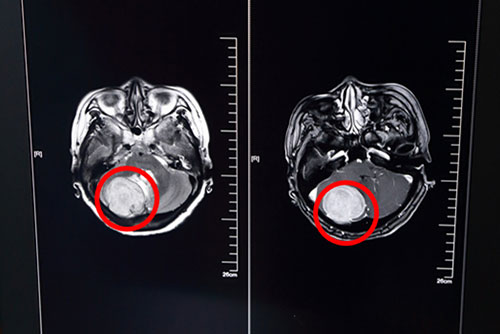

为求进一步治疗,欧女士慕名来到上海蓝十字脑科医院,查头颅MR平扫加增强示:右侧后颅窝单发实性占位病变,增强扫描富血供,病灶与右背侧小脑幕关系密切。原来,头痛的罪魁祸首竟然是小脑幕下肿瘤,而且发现时,瘤体已经42*40*45mm大小。

欧女士术前头颅MRI影像资料:红圈内白色团状物为42*40*45mm大小肿瘤